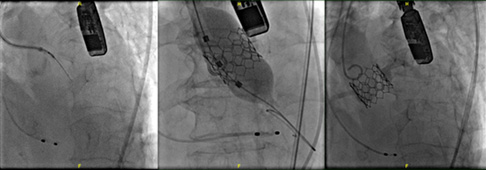

但現在醫學進步快速,有一種叫做 「Transcatheter Valve-in-Valve Replacement,簡稱 ViV-TAVR,經導管瓣膜再置換手術」 的方法,只需要從腿部血管穿一條導管,把新的人工瓣膜送進心臟,放在舊的瓣膜裡面展開,就像幫舊水管加裝新閥門一樣,不需要再打開胸口,就能讓心臟恢復正常運作。

這時候,醫師就會考慮做一種更溫和的方式一一直接把新的瓣膜透過導管,放進舊瓣膜的「殼」裡,讓它像是「套一層新的閘門」一樣,重新控制血液的進出。這種方式就叫做:經導管瓣膜再置換手術(Transcatheter Valve-in-Valve Replacement,簡稱 ViV-TAVR)。

與BASILICA的「電切」不同,Unicorn 技術改採「機械撐開」的方式。醫師將一個特製的雙氣球導管定位在舊瓣膜葉片附近,透過打氣的方式,用氣球力量把葉片推開,形成通道,達到類似 BASILICA 的效果。